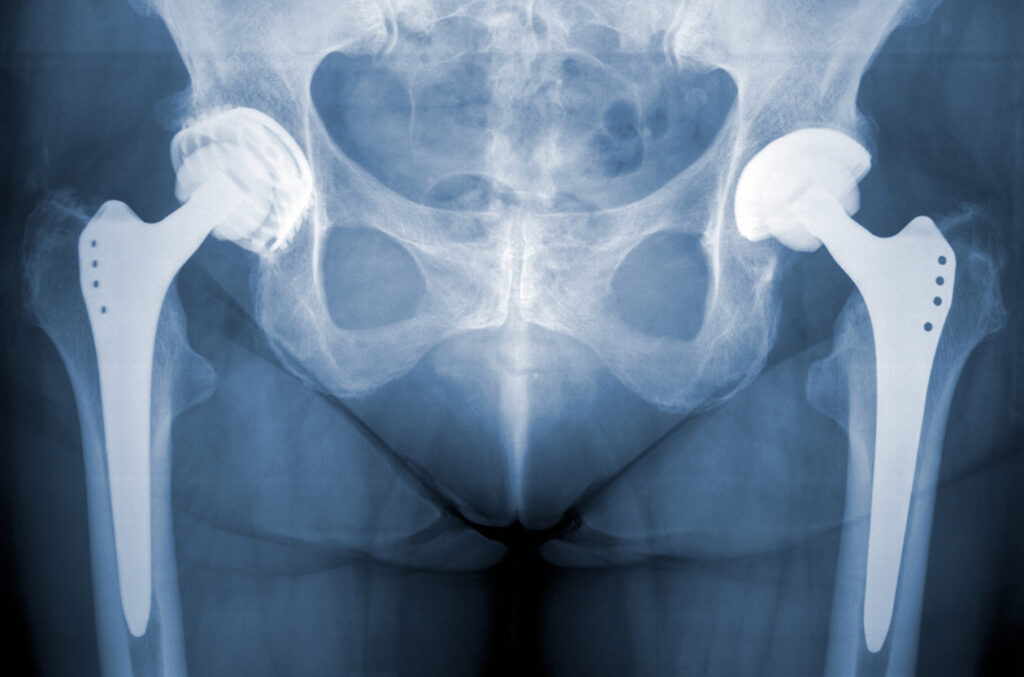

- Internal Fixation. Surgeons use metal screws, plates, or rods to stabilize the bone while it heals.

- Partial Hip Replacement. Only the damaged portion of the hip is replaced.

- Total Hip Replacement. Both the ball and socket of the joint are replaced with artificial components.